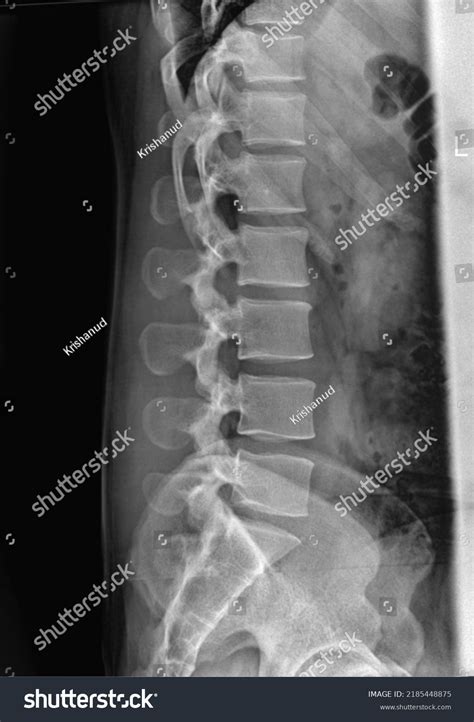

When a technician captures these images, they generally take views from multiple angles—typically an anteroposterior (front-to-back) view and a lateral (side) view. The radiologist then meticulously reviews several specific components of your spine:

• Vertebral Alignment: Ensuring the five lumbar vertebrae are stacked correctly without slippage (spondylolisthesis).

• Bone Density: Assessing if the bone looks healthy or if there are signs of thinning, which could indicate osteopenia or osteoporosis.

• Disc Space Height: While X-rays do not show soft tissue well, the space between the bones can suggest the health of the intervertebral discs. A “normal” space suggests no severe narrowing.

• Vertebral Body Integrity: Checking for any compression fractures or structural changes.

• Soft Tissue Shadows: Looking for unusual shadows that might indicate organ enlargement or large masses in the abdominal area.